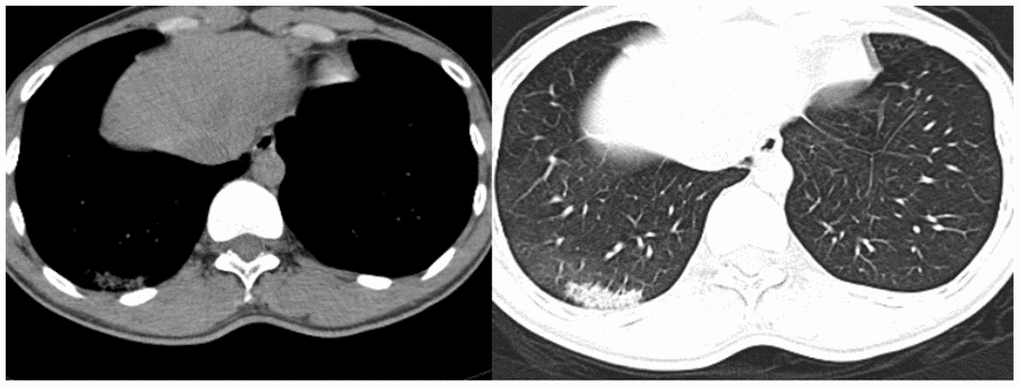

On the first postoperative day, the patient had no obvious cough or sputum production, and his vital signs were stable. By the third postoperative day, however, the patient had developed chills and a high fever, which reached 39.5°C. Routine examination showed that his leukocyte count was 7.7 g/L, hemoglobin 126 g/L, neutrophils 81.3%, lymphocytes 8.9%, monocytes 9.5%, eosinophils 0% and basophils 0.3%. Levels of procalcitonin and c-reactive protein were 0.146 ng/mL and 144.9 mg/L, respectively. A chest CT examination showed a patchy high-density shadow surrounded by a ground-glass opacity in the lower portion of the right lung (Figure 4). After consultation with specialists from the Department of Infectious Disease, the patient was immediately isolated in a single room to prevent potential widespread infection. By postoperative day 5, the patient’s temperature had decreased to 37.2°C, and his cough had significantly diminished. A nucleic acid test for SARS-CoV-2 was positive, and the patient was transferred to the Department of Infectious Disease for further treatment, which consisted of cefoperazone sulbactam 1.5 g every 12 hours, abidole hydrochloride 0.2 g orally three times a day, and oseltamivir 75 mg orally twice a day. The patient’s vital signs remained stable, and his cough and fever eventually resolved.

Figure 4. Chest CT examination of the patient on postoperative day 3.